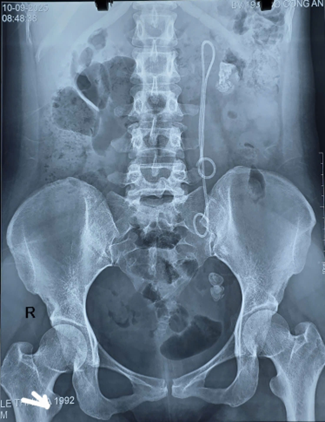

Người phụ nữ 33 tuổi đau tức thắt lưng, tiểu buốt, bác sĩ gắp ra thứ "đáng sợ" bên trong- Ảnh 1.

Hình ảnh XQ của bệnh nhân. Ảnh: Bệnh viện 19-8